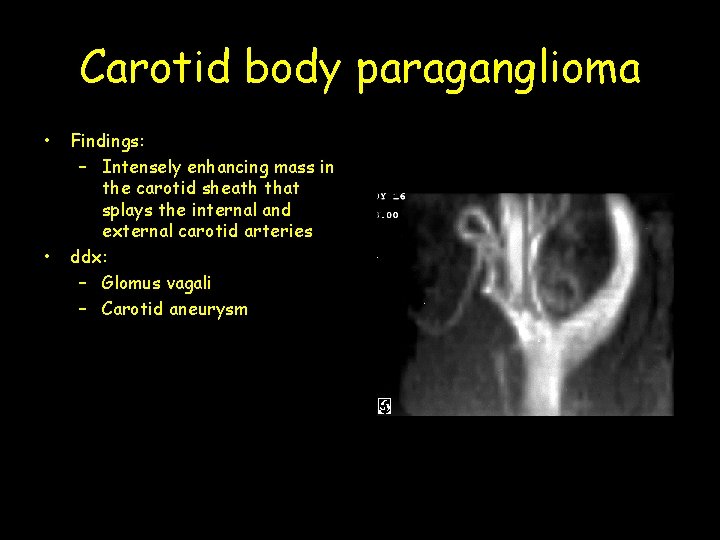

Carotid body paraganglioma • • Findings: – Intensely enhancing mass in the carotid sheath that splays the internal and external carotid arteries ddx: – Glomus vagali – Carotid aneurysm